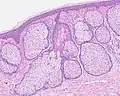

Dermoscopy of sebaceous hyperplasia with digital high dynamic range. Note the multi-lobulated clods with central openings. H&E staining of biopsied lesion of sebaceous hyperplasia: Note the multiple, mature sebaceous lobules attached to the central dilated duct in the upper dermis.

H&E staining of biopsied lesion of sebaceous hyperplasia: Note the multiple, mature sebaceous lobules attached to the central dilated duct in the upper dermis. Sebaceous hyperplasia, lateral right temple marked for biopsy with adjacent malignant melanoma in situ, evolving, medial right temple